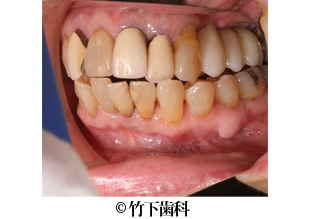

【症例3】右上臼歯部3本欠損のインプラントによる治療

- 治療前

- 治療後

- 治療名

- 右上臼歯部3本欠損のインプラントによる治療

- 費用

- 825.000円(税込)

【内訳】

骨造成は以下に含む

インプラント埋入術 220,000円×3

インプラント上部構造 55,000円×3

- 期間

- 9ヵ月

- 通院回数

- 12回

- 患者様

- 60代女性

治療内容

患者様の症状

歯周病によって、右上5番は動揺が強いために抜歯しました。右上4番、6番は10年以上前に他医院にて抜歯済みでした。いろいろなものを奥歯で食べたいという希望があり、インプラント治療を希望されました。

治療法

右上の5番を抜歯してから2か月後にバーティカルサイナスアプローチによる骨造成をして、同時にインプラントを3本埋入しました。6ヵ月後にインプラントが強固に定着されたのを確認し、3本連結のジルコニアクラウンを装着しました。連結にしたことで、かむ力を分散させて骨への負担を減らしています。

治療結果

審美的にも機能的にも患者様の希望に添えた治療になりました。

そのほか

上顎洞歯槽骨の厚みが3mmしかなく、バーティカルサイナスアプローチにより5mm挙上して8mmのインプラントを埋入することができました。

※治療結果は患者様によって個人差があります。

治療を行う上での 注意点 (リスク・副作用)

出血、腫脹、疼痛、神経麻痺、補綴物のダツリ、破折、インプラント体の破折、咬合違和感、インプラント周囲炎